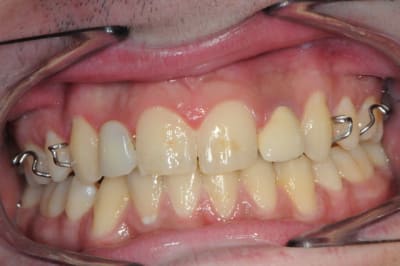

Ton cas est intéressant mais hormis la concavité vestibulaire, à mon avis largement rattrapable avec une expansion,

2 autres pièges attirent mon attention, c'est typique des agénésies des latérales.

1: Absence d'alignement des collets, à gérer impérativement en cours de chirurgie, sinon dent trop courte et inesthétique.

2: espace MD trop étroit à vue d'oeil, attention au type d'implant.

Si le col implantaire est trop large (sup à 3 mm de diam ) tu aura une compression gingivale et disparition des papilles.